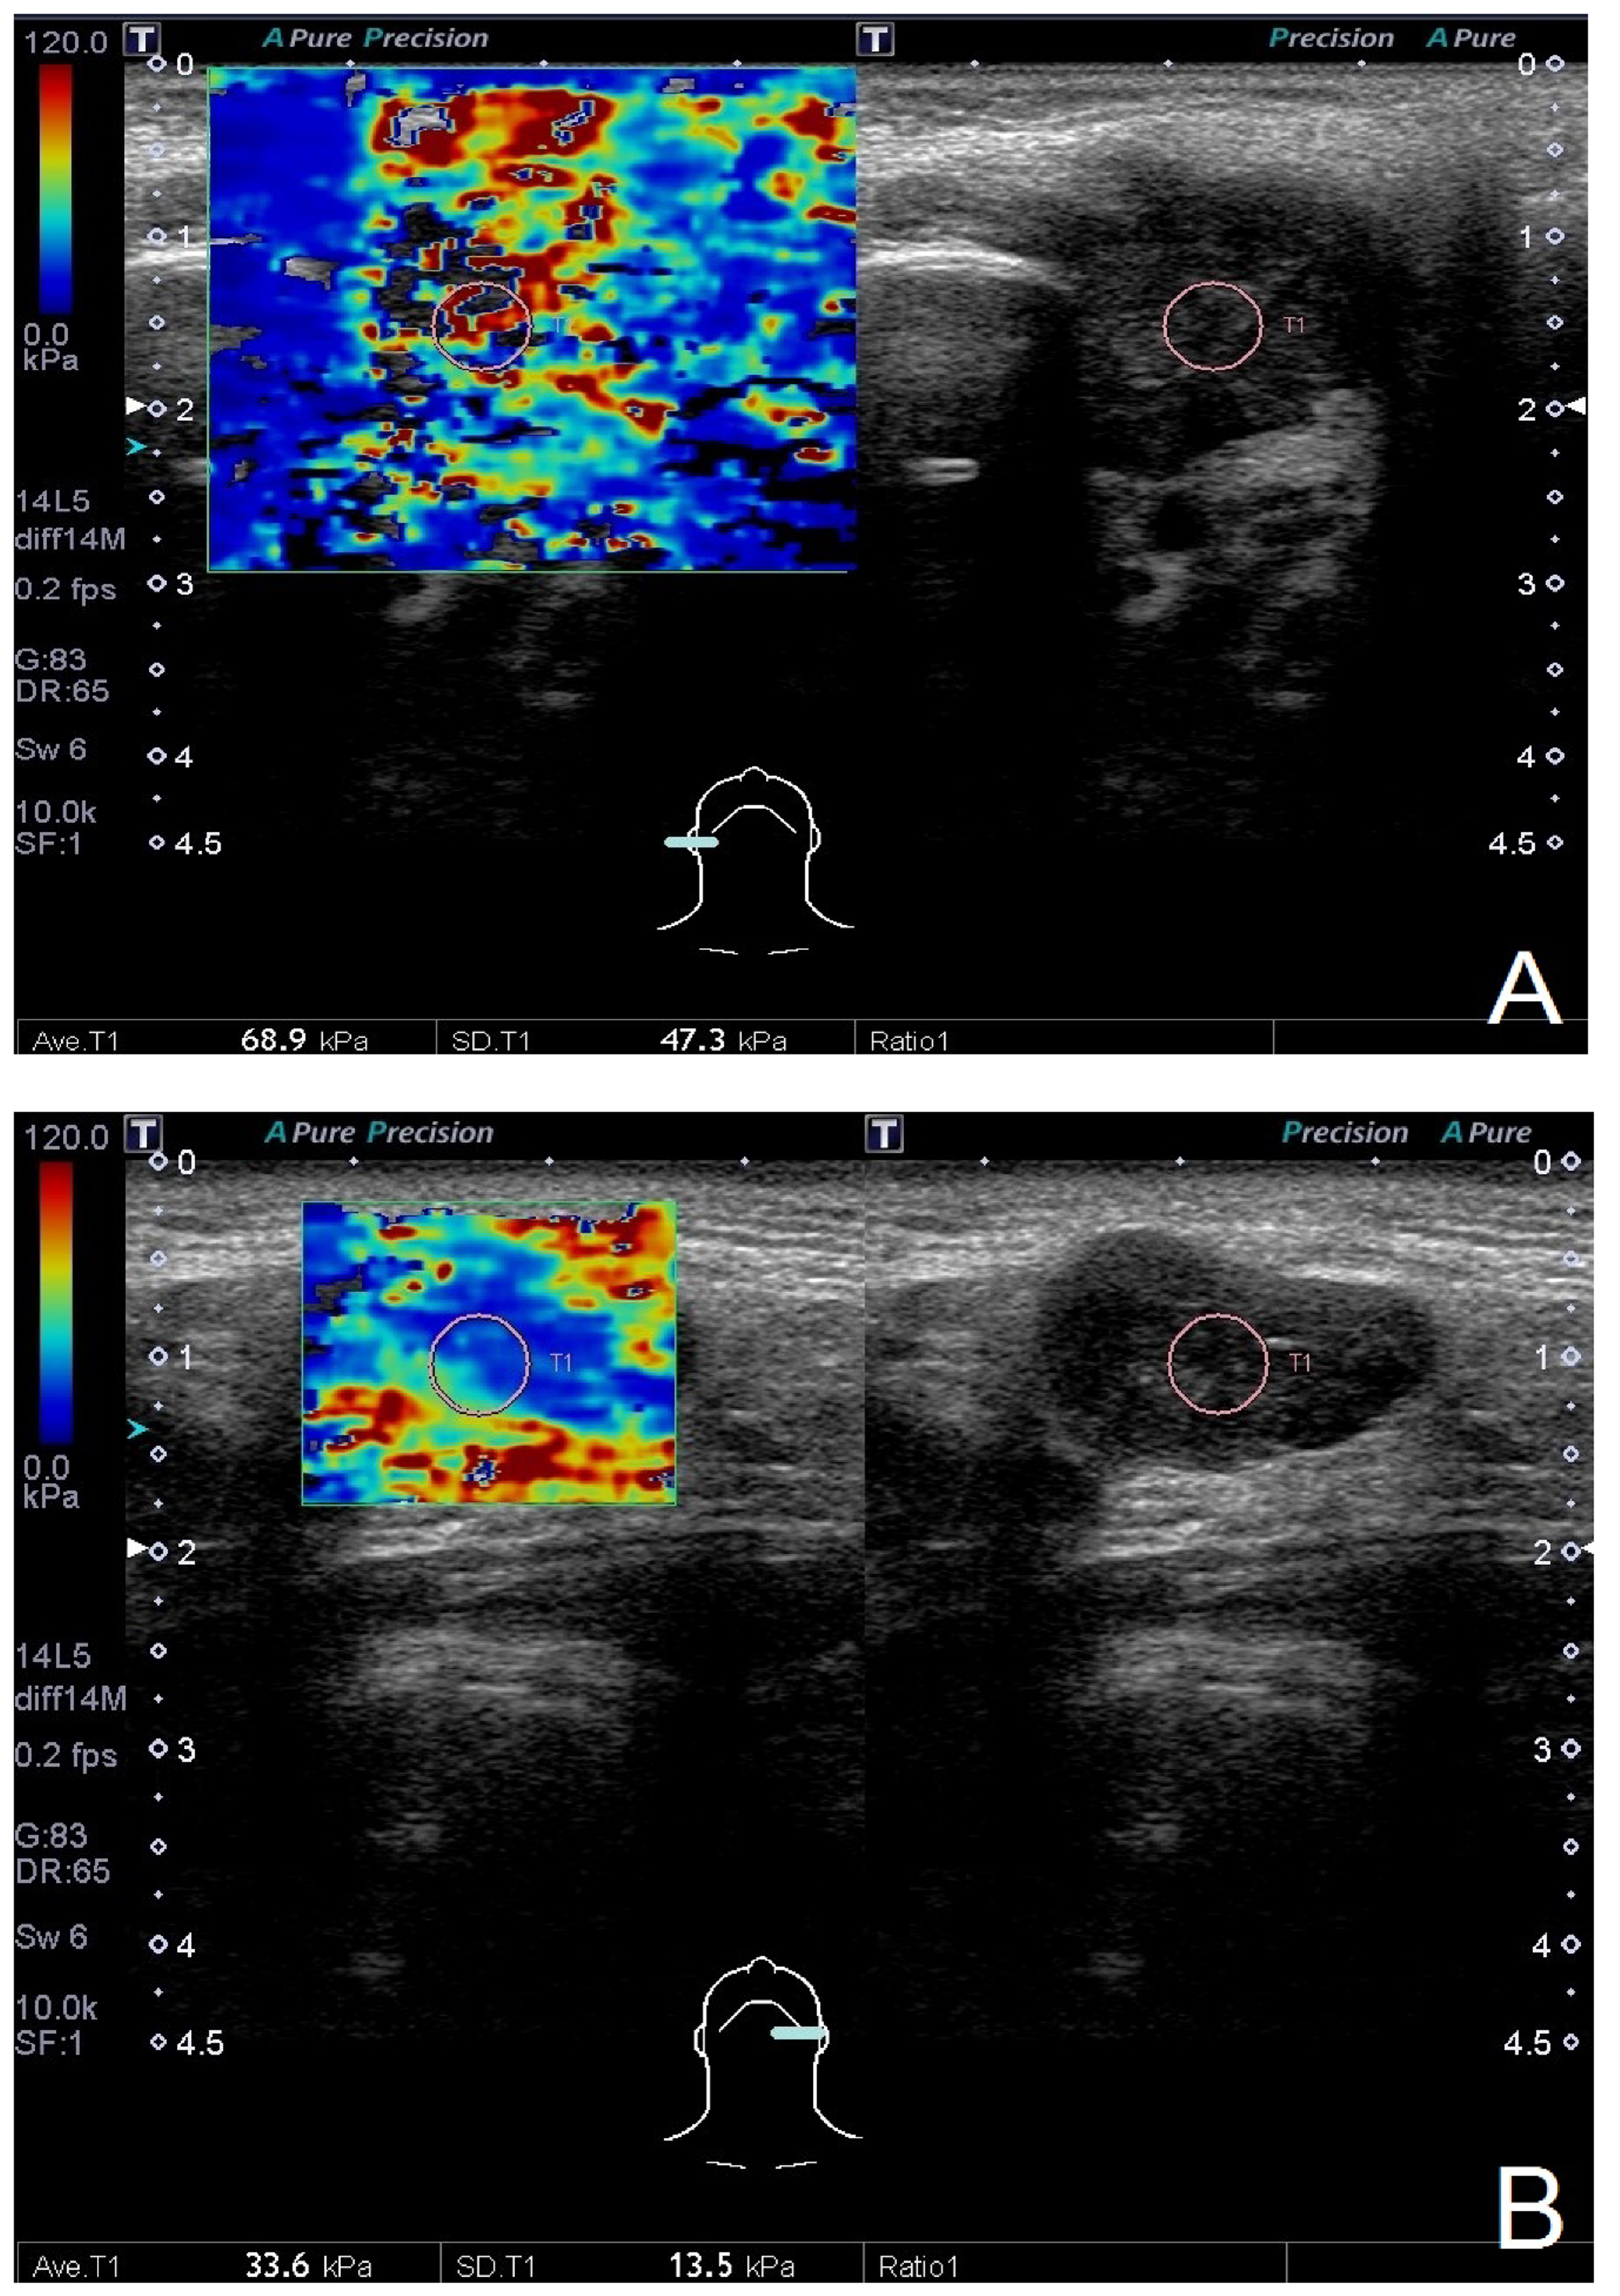

| Average elasticity, kPa | 49.4 (40.3) | 61.8 (32.7) | 0.31 | 60.45 (28.75) | 30.9 (43.1) | <0.01 * |

| Standard deviation of elasticity, kPa | 25.9 (25) | 34.8 (20.4) | 0.01* | 28 (22.4) | 13.7 (26.4) | <0.01 * |